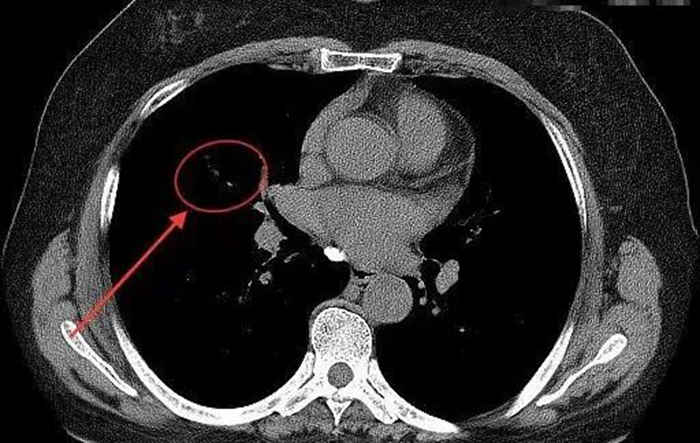

治疗后复查显示,卡堵异物消失

炎性病变也逐渐吸收好转 经过专业的系统治疗后,蒋阿姨各种不适症状彻底消失,检查指标也均趋于正常,术后4天便高高兴兴地出院了。蒋阿姨在我院呼吸与危重症医学科医疗团队的精准施治下,彻底摆脱了折磨她长达八年之久的病痛困扰。